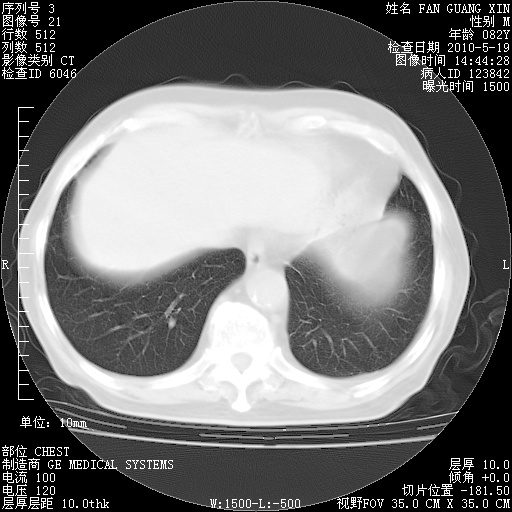

可改为口服强的松40-50mg/d治疗,若病情仍稳定,胸部阴影不再吸收可逐渐减量